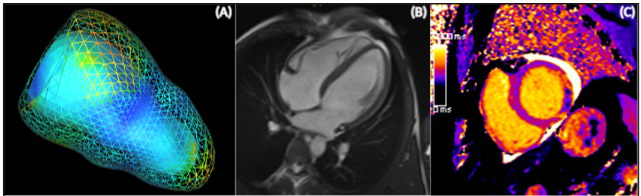

Cardiac Magnetic Resonance Tomography and Myocardial Infarction

The working group on “Cardiac Magnetic Resonance Tomography (CMR)”, led by Univ.-Prof. Dr. B. Metzler, MSc was founded in 2002 and has published over 133 original research papers in peer-reviewed journals since that time. One of its main focuses is on CMR imaging in patients with ST segment elevation myocardial infarction (STEMI), to obtain deeper insights into the pathophysiology of myocardial tissue injury, infarct healing and myocardial remodelling. The assessment of degenerative aortic valve stenosis and CMR-guided transcatheter aortic valve implantation (TAVI) planning is another important focus of the research group. The working group is also involved in randomised, multicentre, multinational clinical trials. The study group is based on close cooperation between the University Clinic for Internal Medicine III, Cardiology and Angiology (Head: Univ.-Prof. Dr. A. Bauer) and the Department of Radiology (Head: Univ.-Prof.in Dr.in E. Gizewski) at the Medical University of Innsbruck. Univ.-Prof. Metzler’s team consists of two associate professors, one senior physician, three fellows and two PhD students as well as a current total of 7 diploma students. Between 2018 and 2020, the working group published 24 peer-reviewed original research articles and obtained nine research grants, including the renowned “Hans-Blömer-Young Investigator Award”, the “Paracelsus prize” and the “Werner-Klein Research Prize”. International cooperation was initiated with the CMR working groups of Prof. Dr. H. Thiele at the University of Leipzig in Germany and Prof. Dr. I. Eitel at the University of Lübeck in Germany, with another seven publications. Future aims include the establishment of extended cooperation with centres in Austria, in order to perform randomised multicentre CMR studies.